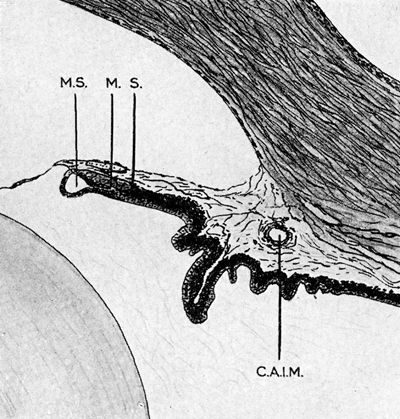

A - Iris y cuerpo ciliar de feto de 5 meses ( ±150mm) MS: seno marginal, M: esfínter de la pupila, S: Michel’s spur (espolón que marca el límite posterior del músculo del esfinter.- C.A.I.M: circulo arterial mayor del Iris

Foto tomada de: Ida Mann ; The development of the Human Eye. 1969. Grune & Straton Inc N.Y

En este momento se puede considerar que la punta del margen en crecimiento representa el borde de la pupila y la porción que muestra pliegues, los futuros procesos ciliares. En este estadío en la punta del margen de la copa, aparece el crecimiento de un iris ectodermico pequeño y grueso creciendo hacia el frente por debajo del mesodermo de la membrana pupilar que en ese período ya esta presente (porción anterior de la túnica vasculosa lentis), es mas grueso en su porción periférica; ya existe la cámara y el ángulo en la cámara anterior, pero los procesos ciliares están indiferenciados.

Continua el crecimiento hacia adelante de la punta del margen, aparecen mas pliegues que ahora ya comprometen las dos capas epiteliales adheridas y al desplazarse hacia adelante, deja atrás una zona compuesta simplemente por dos capas de células epiteliales que será la conocida “Pars Plana”. Los pequeños pliegues se organizan a sí mismos con forma radial en los 360º del margen de la copa, en un número de ± 70-75 pliegues y cada uno hace diferenciación en un único proceso ciliar.

El periodo de mayor crecimiento y diferenciación en el borde de la copa es durante el 5º mes de gestación; como las dos capas del epitelio ectodérmico crecen y se extienden sobre una superficie curva cuando alcanzan la superficie anterior del cristalino, pueden llamarse: capa anterior, la capa externa del epitelio y capa posterior la capa interna del epitelio ectodérmico. La capa anterior es pigmentada, y a medida que crece rebasa el margen e inicia la pigmentación de la capa posterior, cuyas células permanecen en forma cúbica y se pigmentan en forma progresiva, hasta alcanzar la porción de la base del cuerpo ciliar en la raíz del iris.

El Sphinter pupillae inicia su aparición alrededor del 4º mes de la gestación, cuando en el protoplasma de las células cúbicas de la capa anterior, en el extremo del borde iridiano del Seno Marginal aparecen trazas de fibrillas; con el tiempo se desplazan levemente hacia atrás dejando el borde libre y se demarcan claramente de sus células germinales, ya que éstas tardíamente adquieren pigmentación y las células musculares nunca se pigmentan. El esfínter queda levemente sumergido dentro de la sustancia de la parte pigmentada del iris y su límite posterior queda marcado por una cresta conocida como la cresta o espolón de Michel (Michel’s Spur).